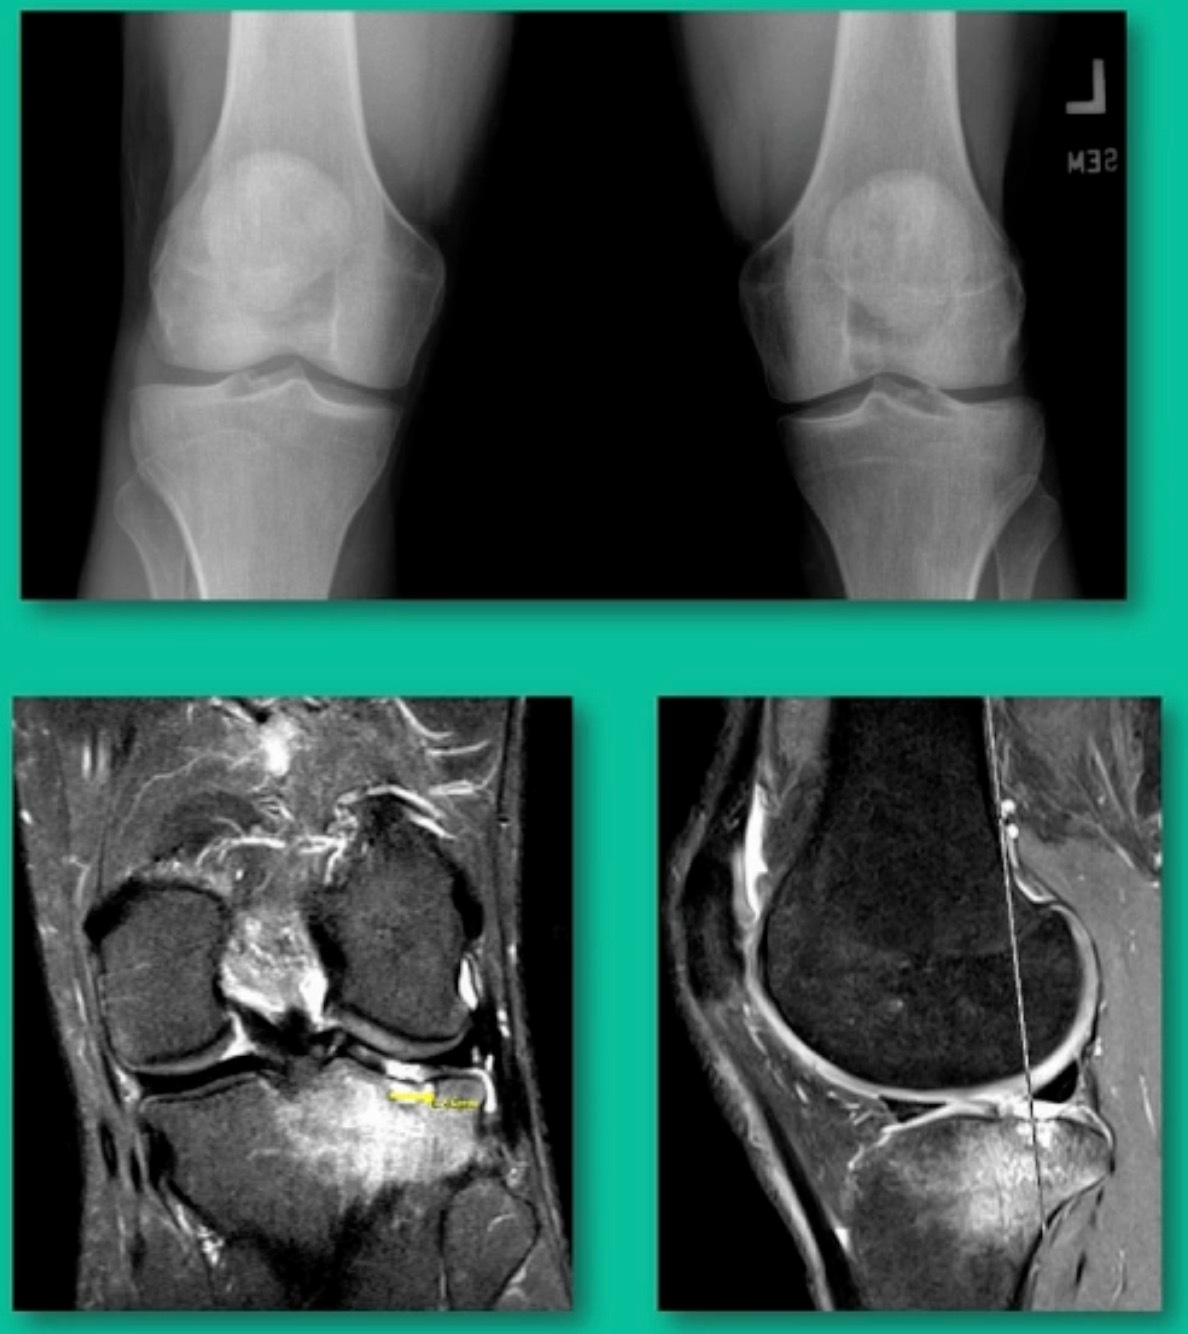

Now a couple of quick cases. This is juvenile OCD. This is the first series of three or four, just juveniles. 14-year-old, intermittent knee pain, lateral femoral condyle OCD (Figure 1).

This is an 11-year-old. Left knee lateral knee pain. Effusions, the same type of classic findings (Figure 3)

Another case example. 14-year-old male tennis player, 10 months of knee pain (Figure 7A).

Now, we’ll shift to the adult. This is a 27-year-old. Right knee swelling, activity-related, and classic failed nonsurgical treatment on the lateral side of the knee.

This is an 18-year-old with a lateral femoral condyle OCD: